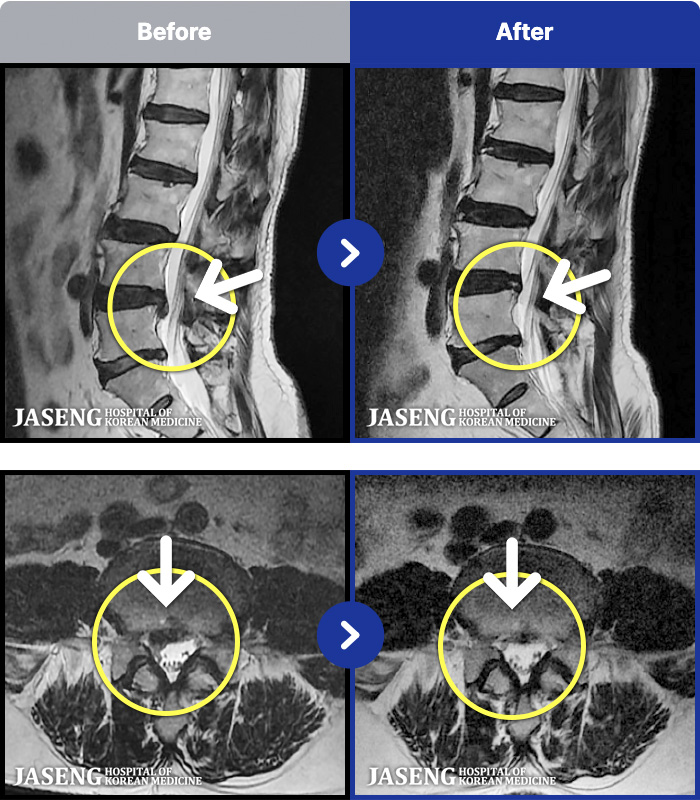

MRI ġ

MRI ũ ʸ Ȯϼ.